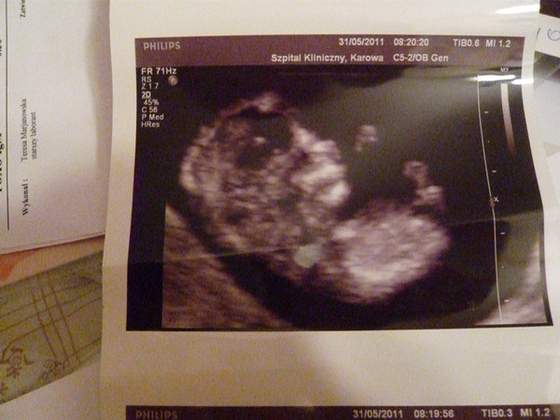

dlatego musze zmienic ginusia po raz 2 :-) wstawiam Moja Kluseczke

i opis badania tak dla waszego porównania:-)